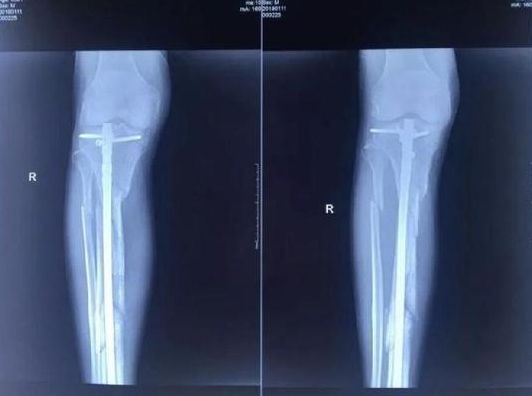

到在地进行殴打,并用事先准备好的铁镐把他的右腿打断成几节。

▲张毅生前遭人殴打致骨折。图片来自北京晨报